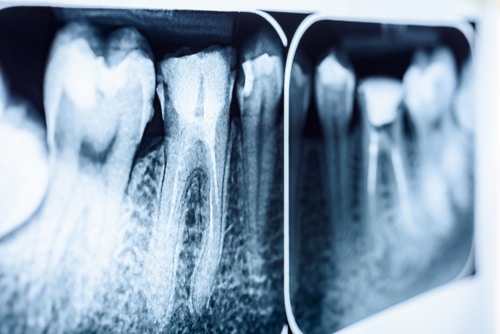

Root canal treatment often suffers from a misunderstanding of what actually happens during the procedure. Many people picture the tooth being hollowed out or the roots being removed entirely. In practice, we target only the infected pulp inside the tooth. That soft tissue houses nerves and blood vessels. When it becomes inflamed or infected, it causes the pain people associate with the need for treatment. By removing the pulp and leaving the roots in place, we preserve the structure that anchors the tooth in the jaw and allows it to continue functioning normally.

To begin a root canal, we create a tiny pathway at the top of the tooth to reach the infected pulp inside. From there, we carefully remove the damaged tissue and clean and disinfect the inner chambers. Finally, we seal the space with a specialized material to prevent bacteria from returning. Once that step is complete, we restore the tooth with a filling or crown so you can bite and chew comfortably again.

We determine the right path through a careful examination and detailed imaging. Dr. Battle evaluates the condition of the tooth, the surrounding bone, and how the infection has progressed. That information allows us to explain your options clearly and recommend the approach that aligns with your long-term oral health.